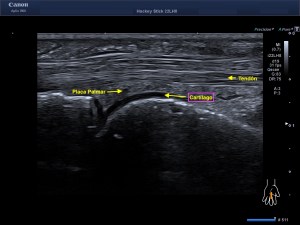

Ecografícamente y debido a su levedad, en el caso de hoy solo observamos cambios en las partes blandas de la cara lateral de la cabeza del quinto metatarsiano, este tejido se muestra heterogéneo, la cortical del hueso ligeramente prominente sin afectación de la misma.